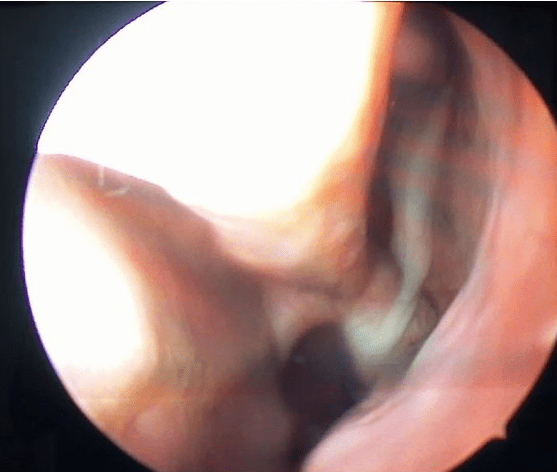

Nasal Endoscopy

A nasal endoscopy involves inserting a thin, rigid tube with a light and camera into the nasal passages to visualize the sinuses directly. This procedure can provide valuable information about the extent of inflammation or any blockages.